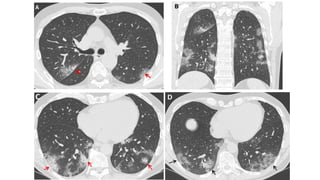

Imagen.

• Rx de tórax influenza que tengan:

• Exploración pulmonar anormal

• Sospecha de neumonía

• Tomografía de tórax:

• Desaturación

• Radiografía de tórax con datos sugestivos de neumonía

• Algunos patrones tomográficos frecuentes en influenza son:

• Vidrio despulido

• Engrosamiento de pared bronquial

• Localización difusa

-Opacidades

redondeadas

-Engrosamiento de

los septos

interlobulares

-Ausencia de

nódulos y de patrón

de árbol en brote

Distribución

periférica típica,

puede ser útil para

diferenciar COVID-19

de influenza.

Imagen. • Rx detórax influenza que tengan: • Exploración pulmonar anormal • Sospecha de neumonía • Tomografía de tórax: • Desaturación • Radiografía de tórax con datos sugestivos de neumonía • Algunos patrones tomográficos frecuentes en influenza son: • Vidrio despulido • Engrosamiento de pared bronquial • Localización difusa Prevención, diagnóstico y tratamiento de la Influenza estacional. Guía de Práctica Clínica: Guía de Referencia Rápida: México, CENETEC; 2020

-Opacidades redondeadas -Engrosamiento de los septos interlobulares -Ausenciade nódulos y de patrón de árbol en brote Distribución periférica típica, puede ser útil para diferenciar COVID-19 de influenza.